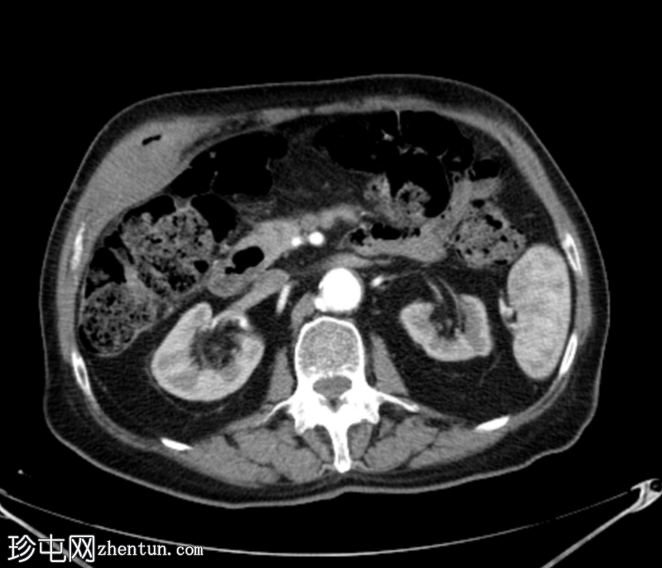

2.png

轴位增强扫描

动脉期

胆囊底部可见一枚较大的(3厘米)高密度结石,胆囊壁增厚并强化,主要位于胆囊底部。胆囊壁可见一小穿孔,感染扩散至胆囊外,并在肝下区可见气体腔。感染进一步扩散至腹壁肌肉,腹壁肌肉内可见脓肿,边缘强化明显,囊性坏死中心,腔内可见气体腔。十二指肠第一段与炎症胆囊粘连。

检查结果提示急性胆囊炎合并腹壁脓肿。